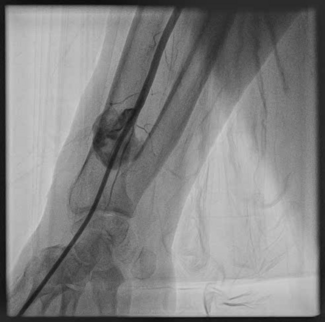

An 84-year-old man with a history of dyslipidemia and hypertension underwent invasive coronary angiography via his right radial artery because of acute coronary syndrome. After the procedure, a palpable pulse was noted in his right forearm,...